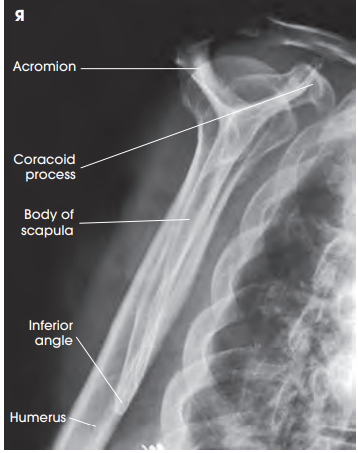

안녕하세요, 오늘은 어깨(shoulder) 촬영방법 중 하나인 shoulder Lateral oblique(Scapula Y view) 촬영법에 대해서 설명하겠습니다. 견갑골이 알파벳Y자로 보여 Y view라는 이름이 지어졌습니다. 이 촬영법은 어깨 dislocation(탈구)가 의심되는 환자 평가에 유용합니다.

영상평가

- body of scapula와 rib이 겹쳐지지 않게 한다.

- Coracoid process(오훼돌기)가 포함되어야 한다.

- 견갑골은 Y자 형상을 하여야 한다.

- 전방탈구의 경우 상완골두가 coracoid process아래에 위치한다

- 후방탈구의 경우 상완골두가 acromioclavicular process 아래에 위치한다